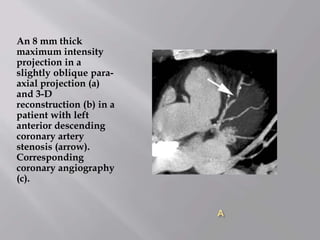

An 8 mm thick

maximum intensity

projection in a

slightly oblique para-

axial projection (a)

and 3-D

reconstruction (b) in a

patient with left

anterior descending

coronary artery

stenosis (arrow).

Corresponding

coronary angiography

(c).